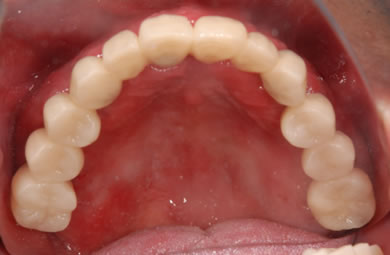

骨再生インプラント治療

| 治療方針 | 骨再生療法にて上顎の骨を増やしインプラント治療にて審美的・機能的回復を行う。 | ||||||||||||||||||||||||||||||||

| 治療内容 | インプラント7本(ソケットリフト)、ハイブリッドセラミック12本 | ||||||||||||||||||||||||||||||||

| 総治療費 | 3,207,924円 | ||||||||||||||||||||||||||||||||

| 治療期間 | 1年6ヶ月 |